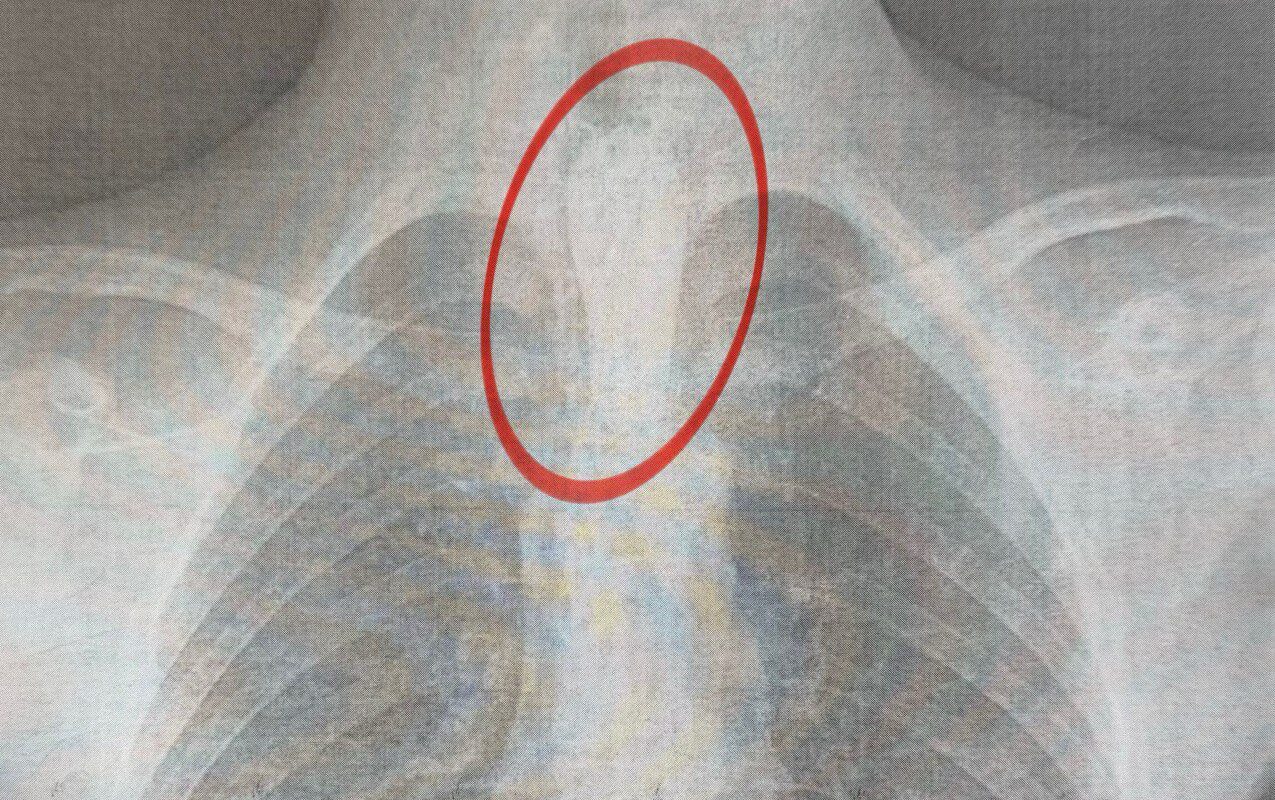

“Стравохід має природні звуження: на рівні шиї, біля аорти та на вході до шлунка. У цьому випадку шматок м’яса зупинився на другому звуженні. Слина постійно виробляється, але не може пройти далі, що викликає сильну слинотечу, відчуття стороннього тіла за грудиною і страх. Дитина не могла нормально дихати”, – розповів торакальний хірург нашого Центру Олександр Колодій.